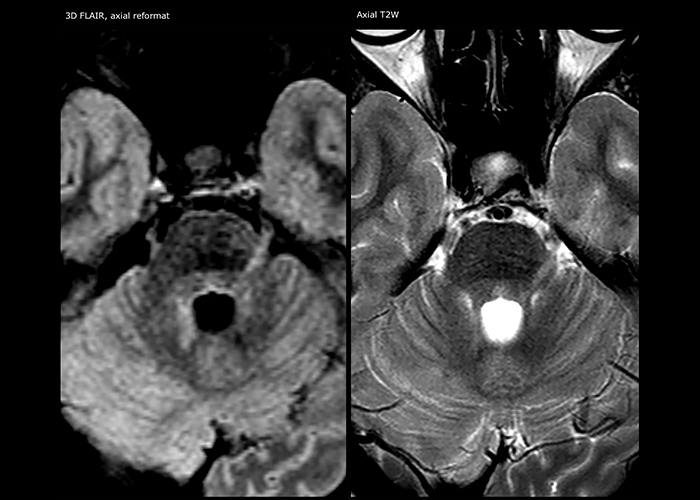

Wenn ein Verdacht auf multiple Sklerose (MS) besteht, muss das Klinikteam schnell zu einer Diagnose kommen, damit die Behandlung so bald wie möglich beginnen kann. „Eine Schwierigkeit bei der Bildgebung ist, dass MS-Läsionen im Gehirn und in der Wirbelsäule sehr klein sein können“, erläutert Dr. Savatovsky. „Wir benötigen eine präzise Bildgebung, um exakt zu bestimmen, wo sich die Läsion befindet, das heißt, wir brauchen hochwertige Bilder in sehr hoher Auflösung, vorzugsweise in 3D[1]. Wir müssen uns sicher sein, ob eine hohe T2-Signalintensität auf MS hinweist oder lediglich aspezifisch ist. Außerdem wünschen wir uns eine sehr gute Visualisierung von aktiven Läsionen.“

„Ingenia 3.0T liefert uns eine sehr gute Bildqualität mit hohem Signal-Rausch-Verhältnis, auch wenn wir die Auflösung ausreizen. Bei FLAIR-Bildern haben wir zum Beispiel eine isotrope Auflösung von 0,9 mm. Ingenia ermöglicht uns die Nutzung von 3D-T1-TSE mit BrainView, was eine bessere Empfindlichkeit als die 2D-Spinecho-Bildgebung[2] und die 3D-Gradientenecho-Bildgebung aufweist. Ingenia liefert auch hoch reproduzierbare Untersuchungen, was bei der MS-Bildgebung wichtig ist, damit Folgeuntersuchungen zu verschiedenen Zeitpunkten auf dieselbe Weise durchgeführt werden.“

Für die MS-Bildgebung im Gehirn nutzt Dr. Savatovsky 3D-FLAIR als Basissequenz, um die Läsionen darzustellen sowie die jeweilige Situation und die Läsionsbelastung zu beurteilen. „Wir zählen die Läsionen an jeder Stelle, um zu bestimmen, ob die Kriterien der Erkrankung erfüllt sind. Dafür wird eine T2-gewichtete Sequenz verwendet, weil unsere Neurologen diese gewohnt sind. Wir vergleichen die Läsionsbelastung unter FLAIR mit einer 3D-T1-Postkontrastsequenz, damit wir feststellen können, ob die Läsionen alt oder neu sind. In der Regel verabreichen wir das Kontrastmittel vor der Aufnahme des Patienten in das System, weil sich dadurch die Untersuchungsdauer verkürzt und die Visualisierung aktiver Läsionen möglich wird, die im Allgemeinen nach mehreren Minuten deutlicher dargestellt werden. Wenn sich eine differenzielle Diagnose als schwierig herausstellt, nutzen wir weitere Sequenzen wie die Suszeptibilitätsbildgebung, da einige fokale MS-Läsionen in der Mitte eine kleine Ader aufweisen[3].“